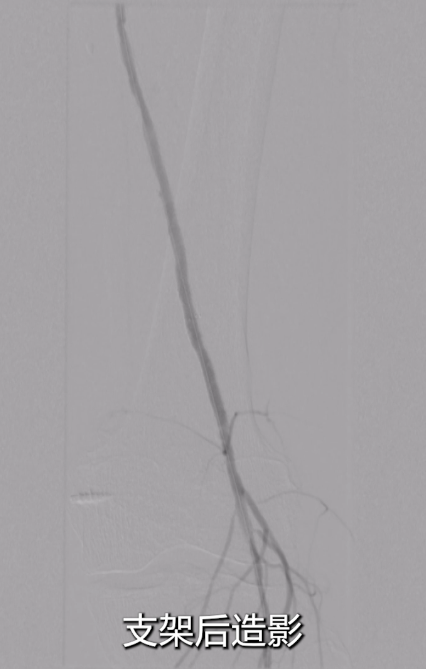

术后效果

即时造影:支架贴壁良好,病变段完全覆盖,膝下腓动脉及胫后动脉显影明显改善,胫后动脉血流可至足趾;

术后ABI:左侧ABI从术前0.32升至0.67,右侧1.09;患者症状改善,左足皮肤发紫发黑明显缓解,静息痛消失。

术后1月复查CTA,血管通畅性良好。给予双通道抗凝+抗血小板治疗,预防血栓再形成。